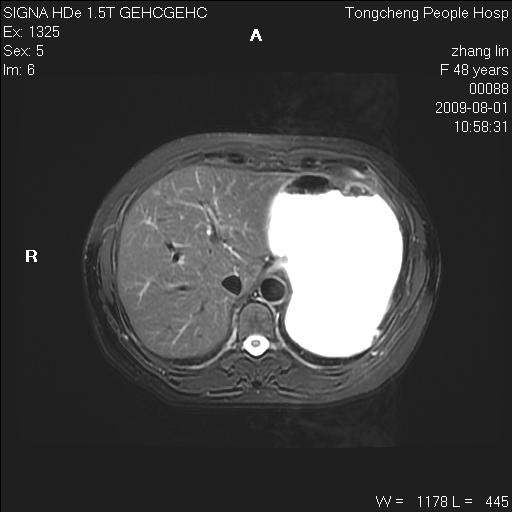

女,48岁。健康体检,彩超发现右肾占位性病变。平素健康。

临床诊断:右肾占位性病变,性质待定(囊肿?肿瘤?)。

上中腹部mr平扫+增强扫描,图像如下:

右肾上极见一类圆形病灶,t1wi呈等信号t2wi呈等高混杂信号,三期增强无强化,边界清---考虑囊肿出血。

同反相位均表现为等信号,病变无强化,考虑含蛋白的囊肿可能,弥散加权相或许有些帮助,

肝囊肿